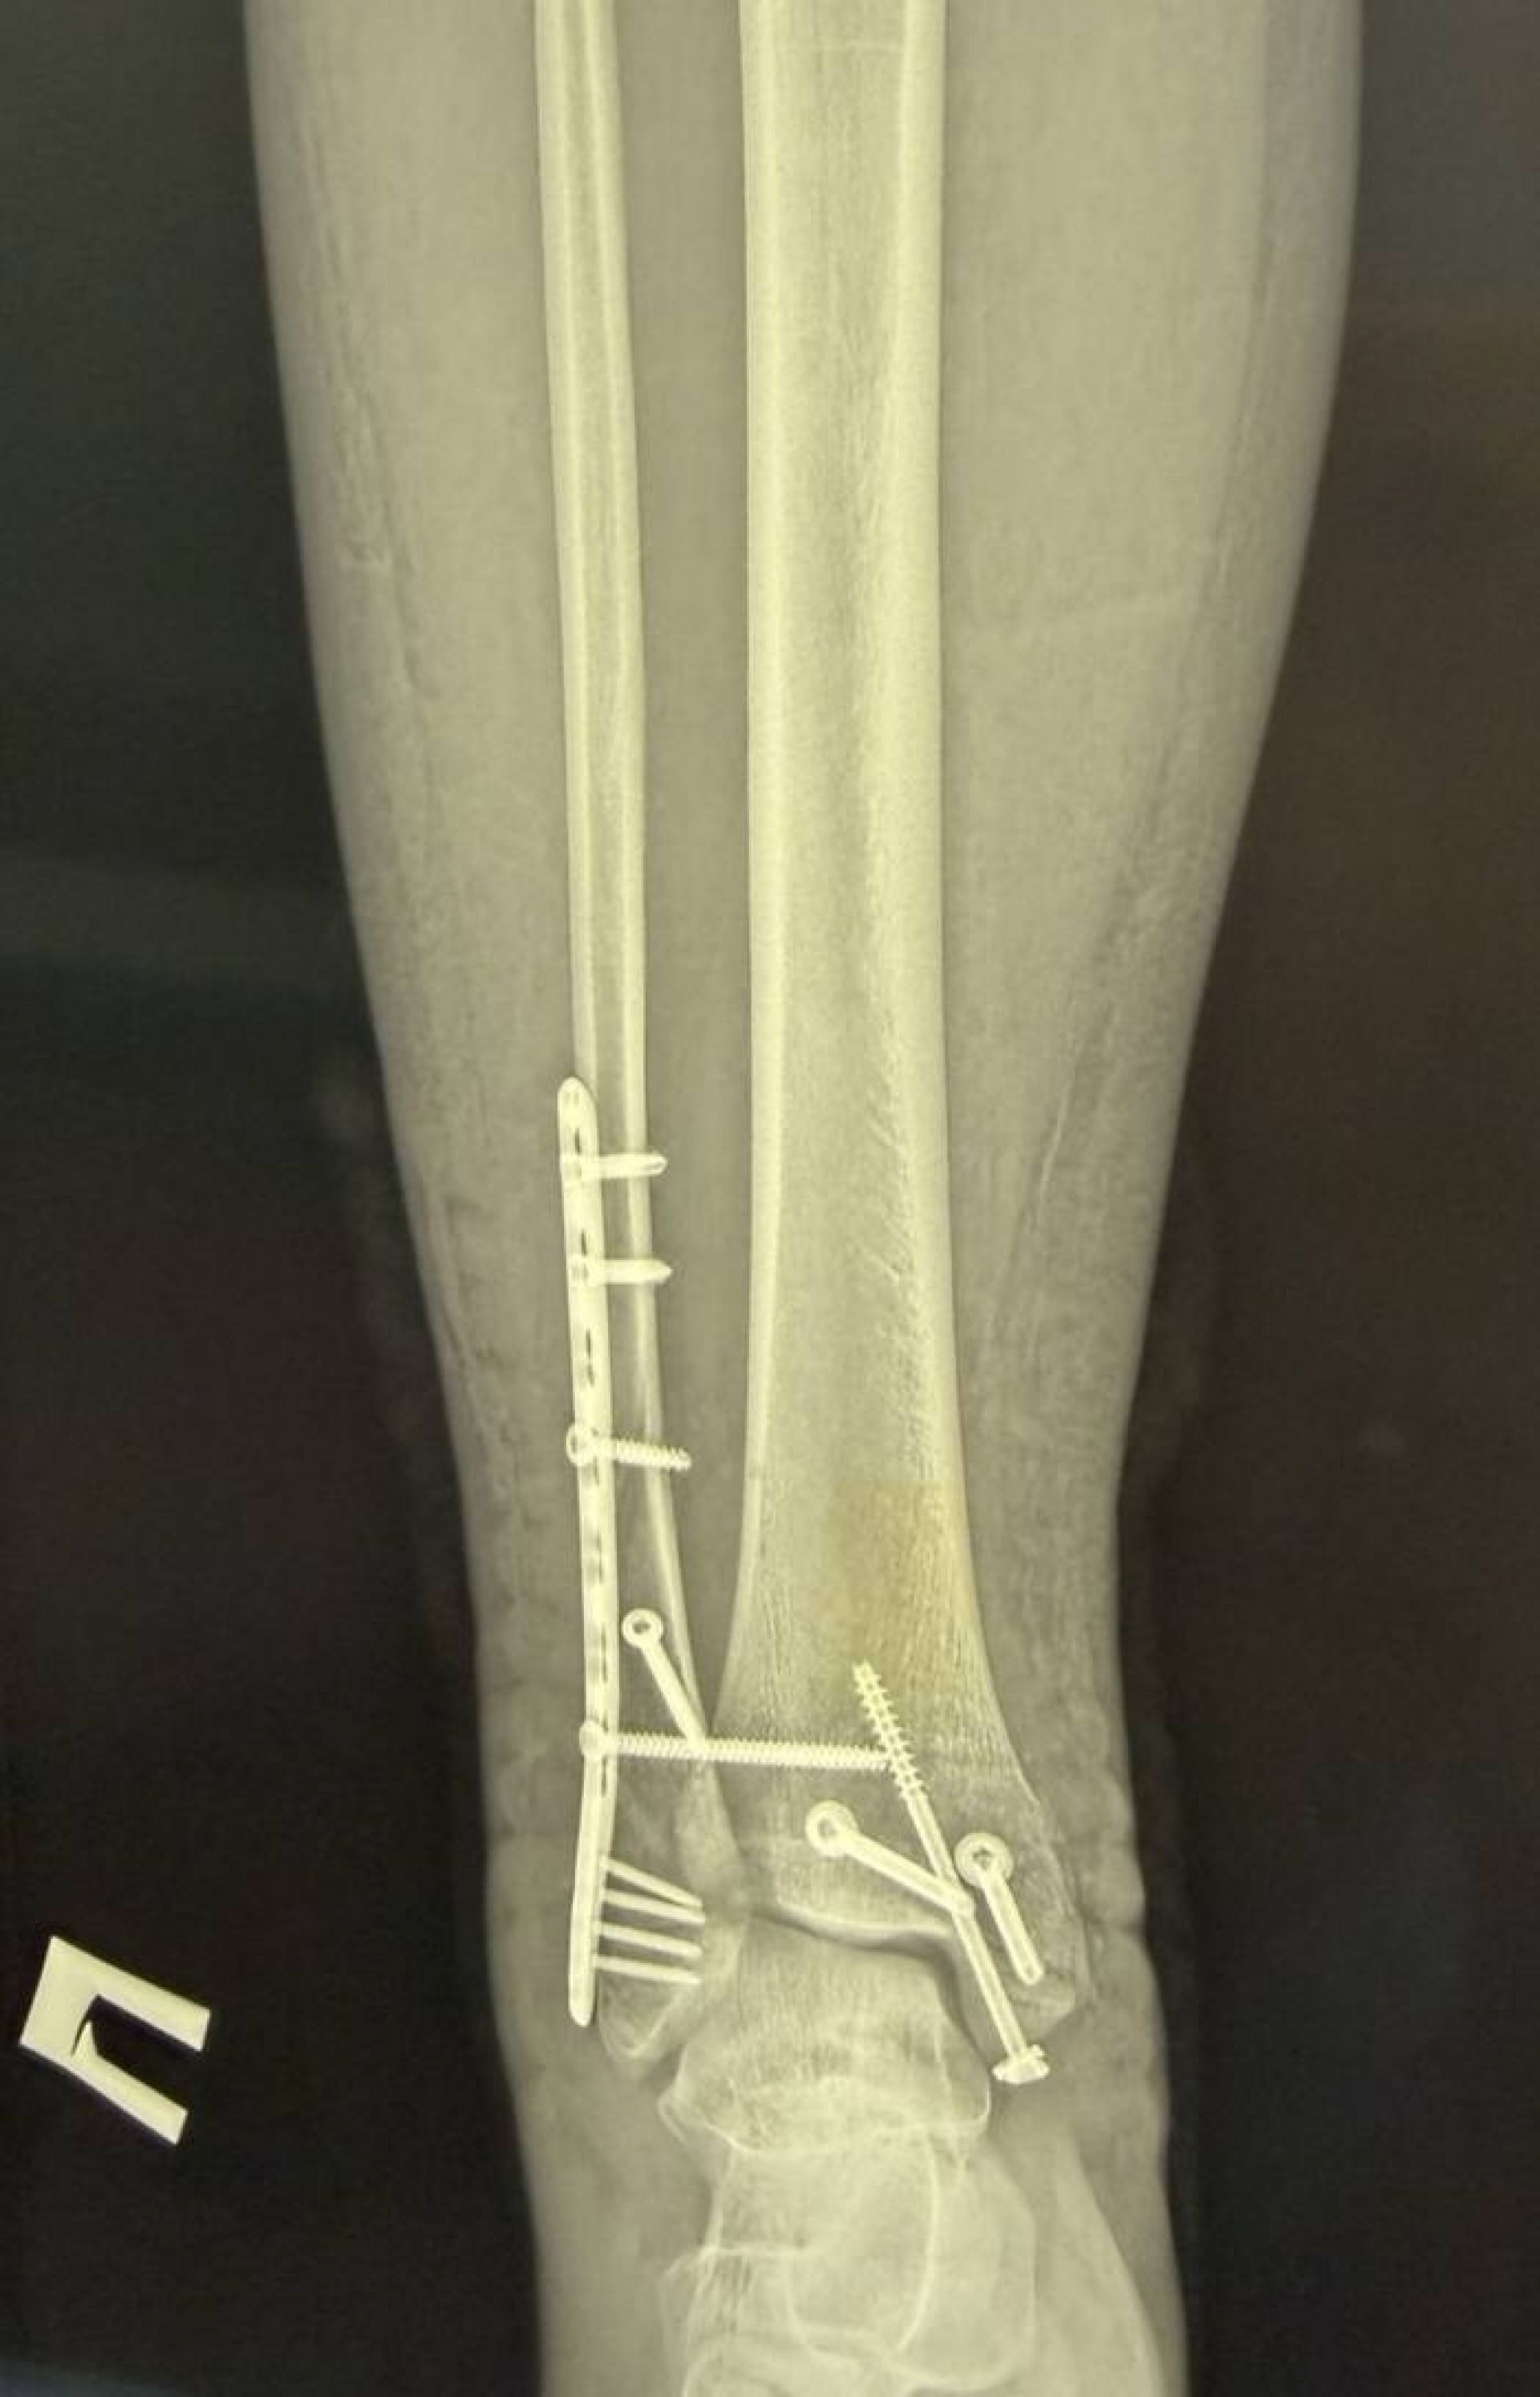

Хлопець звернувся до травмпункту, і обстеження показало, що він має не один, а цілих три складних переломи кісток гомілковостопного суглоба зі зміщенням.

Після госпіталізації та проведення додаткових обстежень (КТ) для максимально точного планування, фахівці лікарні провели складне оперативне втручання.

Головна мета операції полягала у тому, щоб зібрати всі кісткові уламки та повністю відновити стабільність суглоба. Хірурги виконали:

1. Зіставлення уламків малої гомілкової кістки та фіксацію її пластиною і гвинтами.

2. Репозицію переломів великої гомілкової кістки з фіксацією гвинтами.

3. Фіксацію суглоба спеціальним гвинтом для відновлення його стійкості.